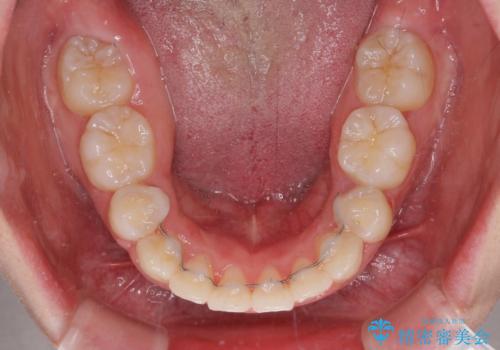

著しい叢生と顎骨のズレ ワイヤー装置による抜歯矯正

アンカーなどをうまく使用して、3年の期間を要してきれいに仕上げることができました。

- 矯正治療後の保定が不十分だと後戻り(元の位置に戻ろうとする動き)をします